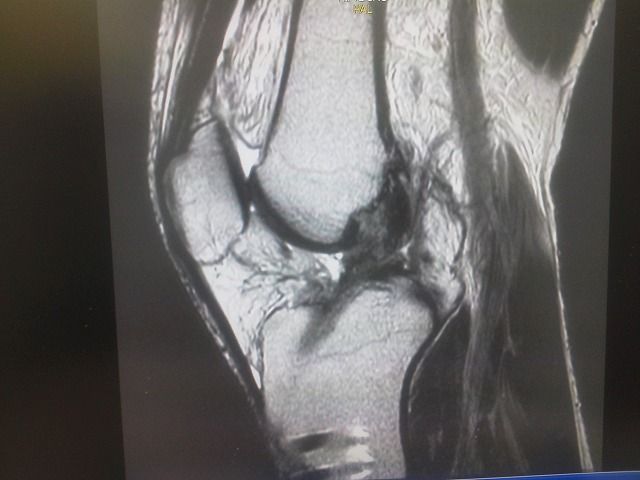

ヤマハのトップライダーの選手です。

本人の強い希望で、右膝前十字靭帯の手術後、再断裂で1か月での参戦です。

ストレッチ、EMSで強化しました。

柔軟な筋腱作りとテーピングが、結果を出しました。

内側広筋と外側広筋を使用したテーピングは威力を発揮します。

昨日の全日本選手権に参戦!  全日本ランキング2位でしたが

結果はやはり・・・でした。 しかし、3時間完走で上位ゲットしました。

ポテンシャルは高いです。

保存的治療でも十分戦えるのです!